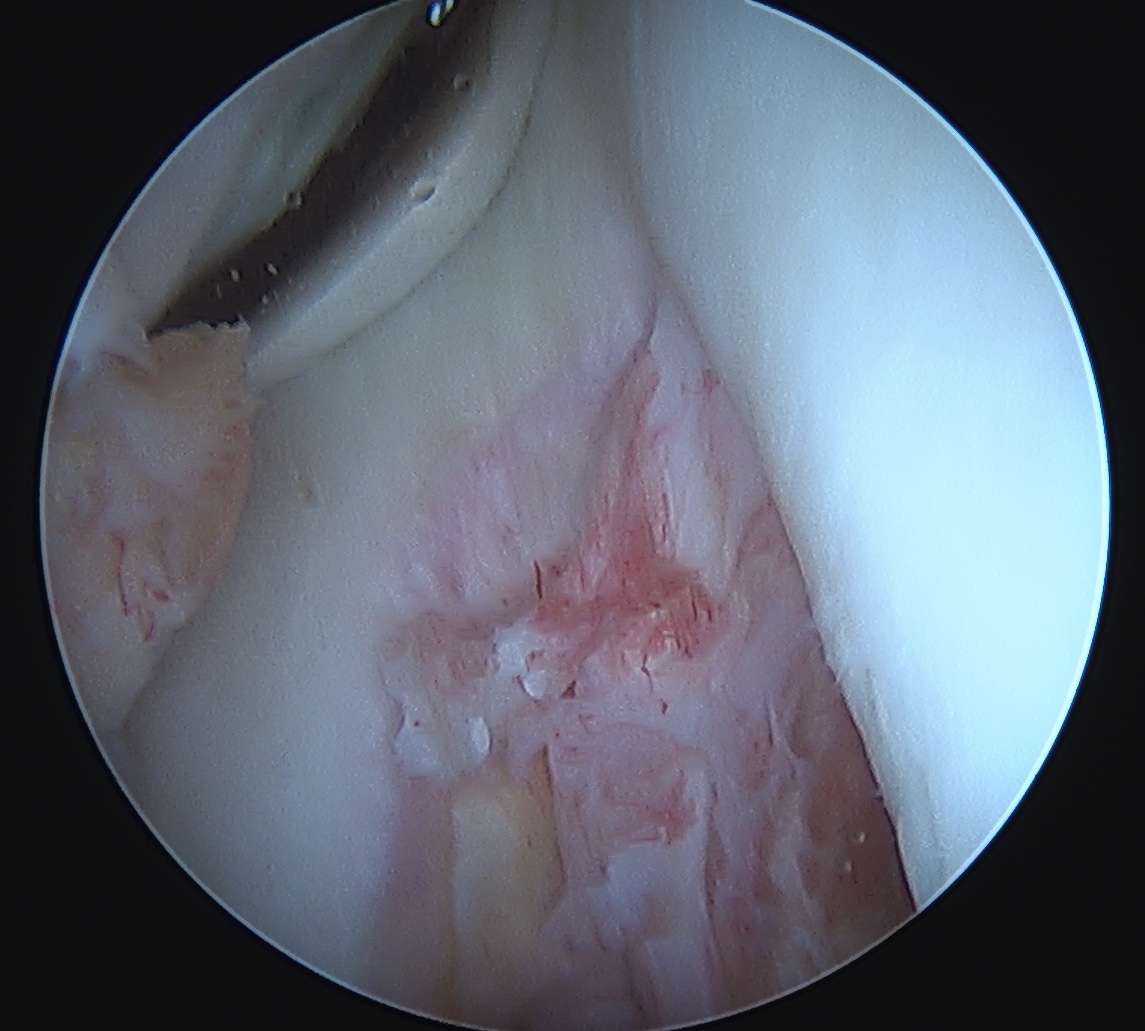

Arthroscopy

May miss tear as is extra-synovial

Chronic PCL tear from femur

Acute PCL femoral avulsion

Apparent ACL laxity due to PCL tear and posterior tibial sag; ACL tension restored with anterior drawer